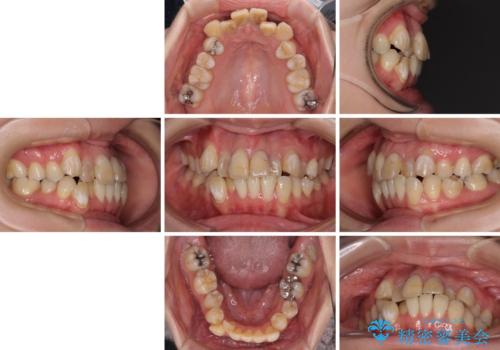

歯並びだけでなく、歯の色も明るくなり、すっきりとした口元の印象となりました。

- 治療期間

- 2年8ヶ月

- 治療回数

- 30回以上

- 治療費の目安: 135万円(税込)費用は治療当時の料金となります